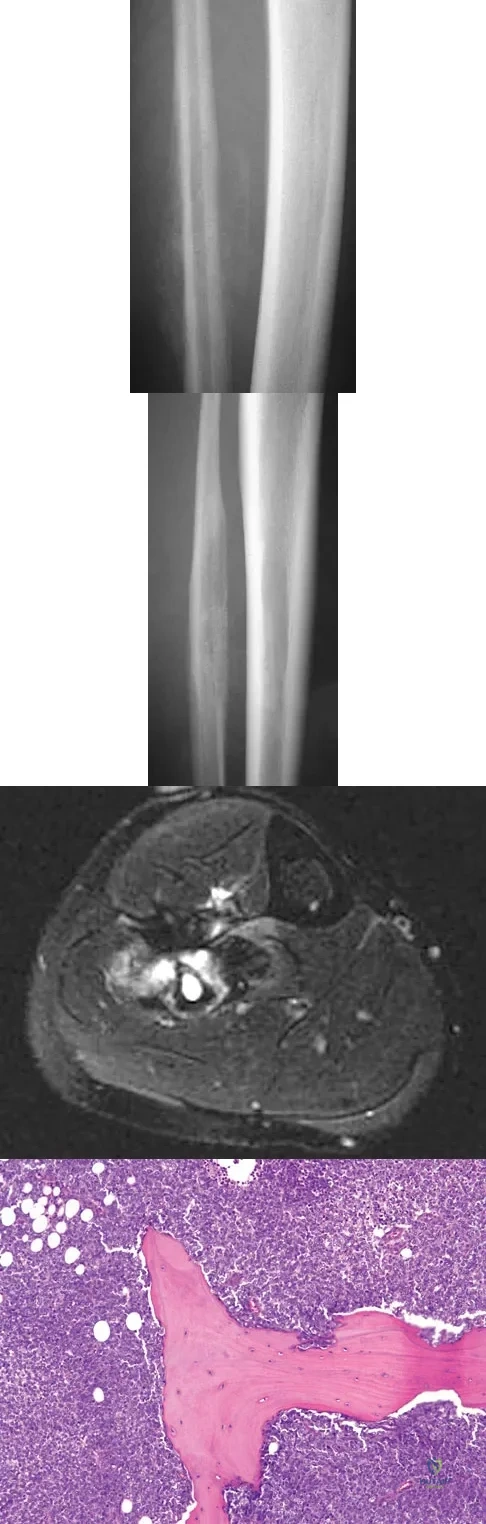

A 16-year-old girl injured her hip in a fall. Radiographs are shown in Figures 14a and 14b. She denies any history of pain prior to the fall and is currently asymptomatic. A bone scan, MRI scan, and biopsy specimens are shown in Figures 14c through 14f. What is the most likely diagnosis?